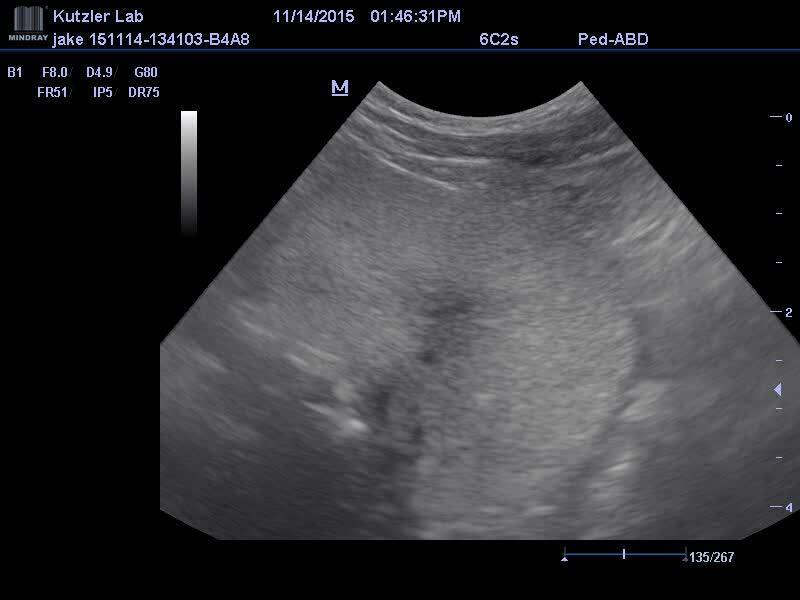

Canine prostate, transabdominal ultrasonography

Transabdominal ultrasonography is the best imaging modality for evaluating the prostate because it allows the prostatic parenchyma to be visualized. This video clip illustrates a transabdominal ultrasonographic examination of the canine prostate in a transverse plane, going from caudal to cranial orientation.

Courtesy of Dr. Michelle Kutzler.